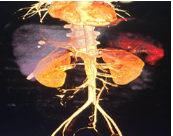

Contrast-enhanced CT of abdomen and pelvis revealed Grade IV liner laceration involving segments VI & VII of Right lobe of liver with 11 X 10mm pseudoaneurysm noted in segment VI/ VII of liver arising from post sectoral branch of right hepatic artery.

After stabilization, the patient was taken for transarterial embolization of pseudoaneurysm through the right femoral artery approach. Post-procedural angiogram revealed no flow into pseudoaneurysm and retained normal flow to the rest of the branches of the right and left hepatic arteries. Post-procedure period was uneventful.